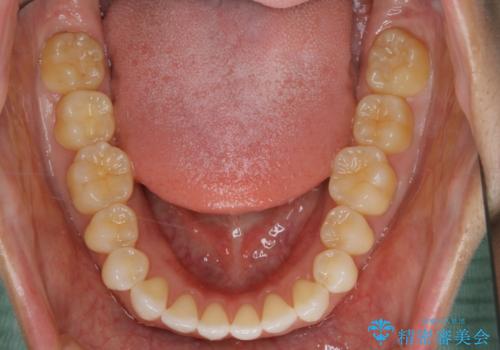

すきっ歯を治したい。インビザライン・ライトによる矯正治療

- 正中離開を気にされて来院された患者様です。

インビザラインでの治療を希望され、正中離開のみ治したいとのことだったので、インビザライン・ライト(片顎)での治療を選択しました。

インビザライン・ライトは枚数が少ないため歯の移動量に限界がありますが、短期間での治療が可能です。